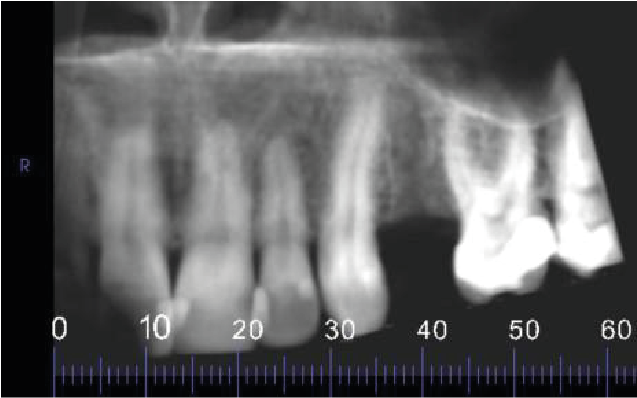

Image 1: Reconstructed Panoramic Image